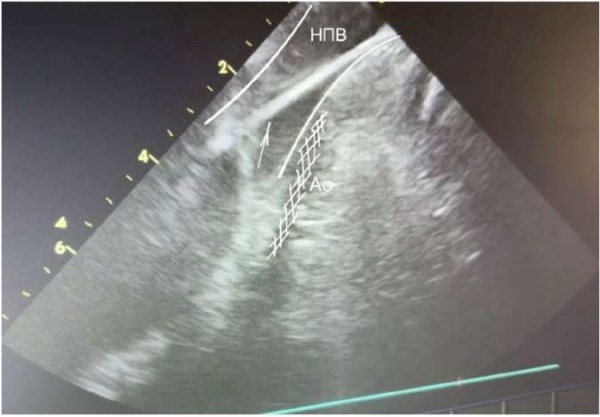

Использование препарата рефралон (кавутилид) для медикаментозной кардиоверсии в остром периоде радиочастотной изоляции легочных вен у пациентов с различными формами фибрилляции предсердий

Фибрилляция предсердий (ФП) является самым распространённым патологическим нарушением ритма сердца. В общей популяции ФП встречается с частотой от 1 до 2%, при этом вероятность возникновения заболевания ...